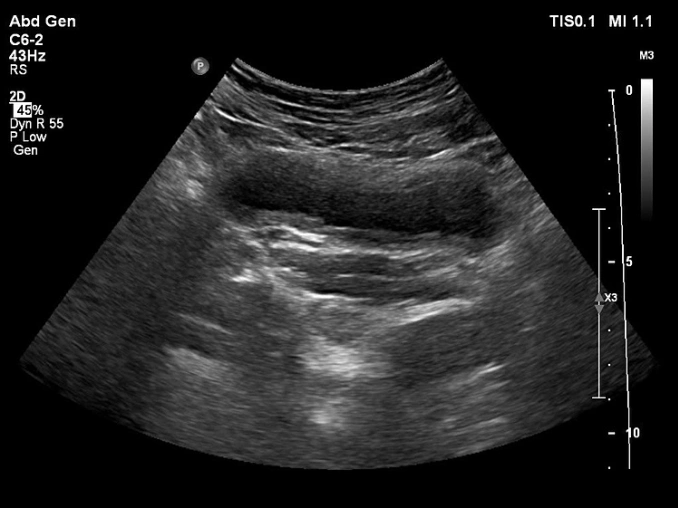

Hình ảnh siêu âm ghi nhận tình trạng viêm. Ảnh: Bác sĩ cung cấp